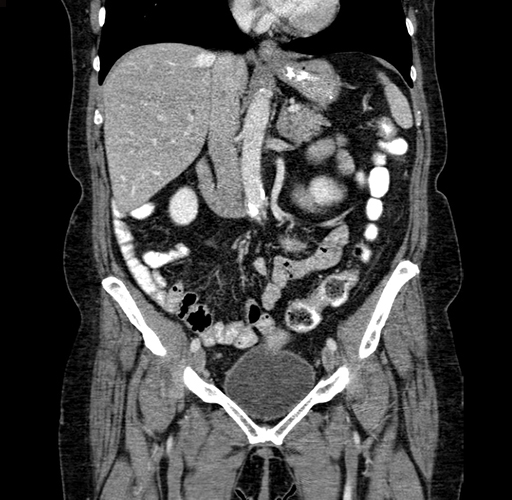

Coronal Venous